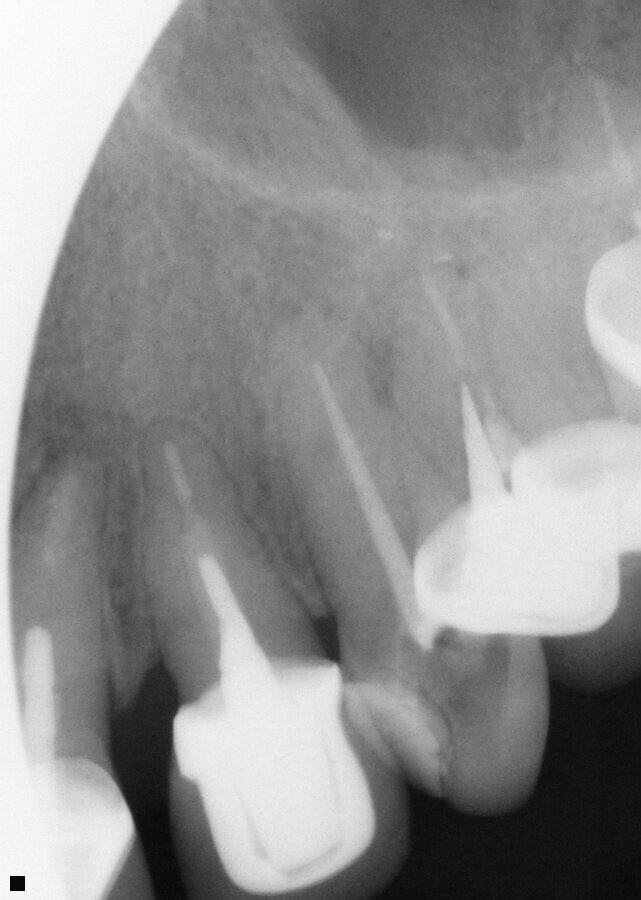

Fig. 16: Patient presented with percussion and hot sensitivity on the lower first molar that she reported was increasing over the past week.

Fig. 17: Instrumentation was performed with ExactTaperH DC files and single cone obturation with Bioceramic Root Canal sealer completing the endodontic treatment preserving the cervical tooth structure during the treatment.

A 62-year-old female patient presented with the complaint of sensitivity to chewing and hot foods and beverages on tooth 19 (mandibular left first molar) that had been increasing over the past week. Examination noted an old amalgam on the tooth that appeared intact to the explorer. A radiograph was taken, and slight apical widening was noted on both root apex on the tooth (Fig. 16). The tooth was responsive to testing with heat with a prolonged response of a minute or so. No cold sensitivity was elicited when tested. Both teeth also tested to slight responsiveness to percussion stimuli. Patient was informed that based on the tooth’s presentation it was recommended that endodontic treatment was indicated. The patient agreed to treatment.

The tooth was isolated with rubber dam, and the old amalgam restoration was removed and access performed with canal orifice identification. The SX file (ExactTaperH DC) was utilized to enlarge the canal orifice and aid in further file instrumentation. The three canals were explored with stainless steel hand files to working length starting at a size 10 and progressing to a size 20. The canals were then instrumented to working length with the GP file. Each canal was instrumented with ExactTaperH DC files starting with the S1, then followed by the F1, F2 and F3 in the mesial-buccal and distal-buccal canals of the molar. The canals were irrigated by alternating between sodium hypochlorite 3 percent (Vista Apex) and 17 percent EDTA solution (Vista Apex) during instrumentation and at completion. The canals were then dried with paper points (ExactTaperH DC) matching the size of the final file used. Bioceramic Root Canal sealer was mixed and dispensed on a pad. A gutta-percha cone (ExactTaperH DC) matching the final file size for each canal was coated with sealer and each canal was obturated in a single cone technique. The excess cones were cut off at the canal orifice and obturation was completed (Fig. 16). A temporary restoration (Fermit-N, Ivoclar Vivadent, Buffalo, N.Y.) was placed into the tooth and the patient was appointed to restore the tooth.